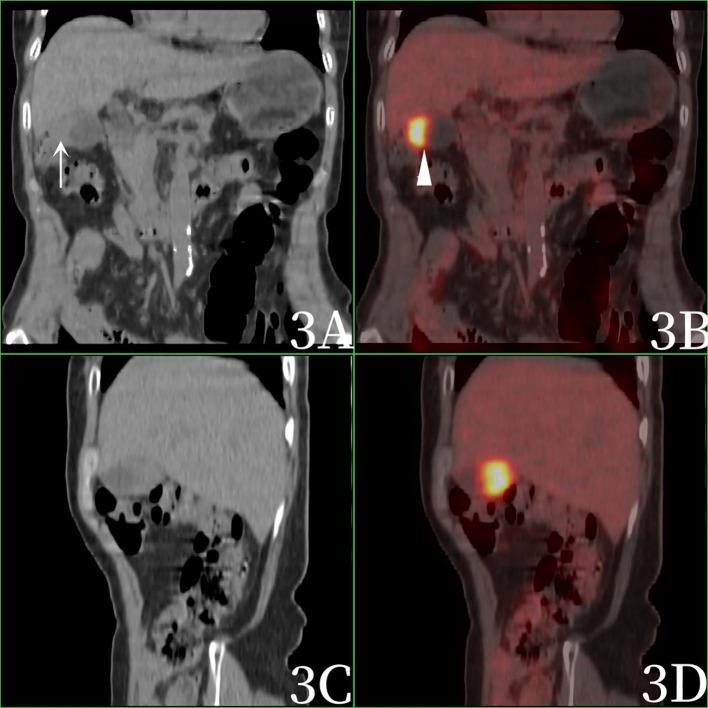

A 69-year-old female patient presented with recurrent intermittent right upper abdominal pain for more than 1 year, followed by nausea and vomiting for 3 hours, without fever, dizziness, chest tightness and other symptoms. Complete CT, MRI, PET/CT and related laboratory tests, CEA (-), AFP (-), Ca199 224.50U/mL ↑,F-FDG PET/CT images showed uneven thickening at the bottom of the gallbladder, slightly increased gallbladder volume, eccentric and localized thickening of the gallbladder body wall, nodular soft tissue density shadow, clear boundary, smooth gallbladder wall, presence and smooth hepatobiliary interface, increased FDG radioactivity uptake, SUVmax was 10.2.The tumor was resected after operation and was diagnosed as gallbladder inflammatory pseudotumor by postoperative pathology.

一名69岁女性患者,反复间歇性右上腹疼痛1年余,伴恶心、呕吐3小时,无发热、头晕、胸闷等症状。完善CT、MRI、PET/CT及相关实验室检查,癌胚抗原(CEA)(-),甲胎蛋白(AFP)(-),糖类抗原199(Ca199)224.50U/mL↑,F-FDG PET/CT图像显示胆囊底部不均匀增厚,胆囊体积略增大,胆囊体壁偏心性局限性增厚,呈结节状软组织密度影,边界清晰,胆囊壁光滑,肝门界面存在且光滑,FDG放射性摄取增加,最大标准摄取值(SUVmax)为10.2。术后切除肿瘤,术后病理诊断为胆囊炎性假瘤。